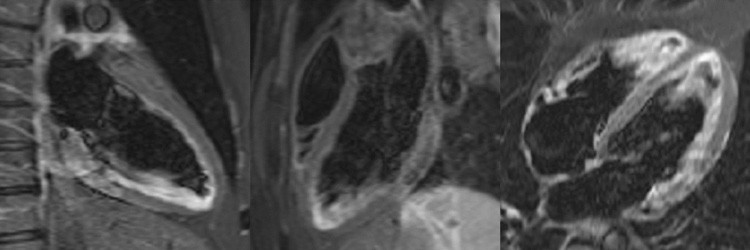

Figure 6A : Séquence T2 STIR - Coupes petit-axe

Figure 6B : Séquence T2 STIR - Coupes long-axe

Présence d’une zone d’œdème myocardique inféro-latéro-basale et inféro-basale avec un hyper-signal T2 (zones blanches, flèches jaunes), comparé au reste du myocarde en iso-signal (le reste du myocarde est gris).

Astuce quant à l'analyse du T2-STIR

- La séquence de T2-STIR inclut une préparation de l’aimantation qui permet d’annuler le gras et le sang. Ainsi, on peut retenir que la seule entité qui est théoriquement censée être en hypersignal est l’œdème myocardique.

- Cependant, veuillez noter ici qu’une partie du sang n’a pas correctement été annulée au niveau des apex du VG et du VD. Il s’agit d’un artéfact classique sur ce type de séquence, qui correspond à des globules rouges moins en mouvement au niveau de l’apex, et qui sont donc moins bien annulés.

- Enfin, retenez que le principal avantage de la séquence de T2-STIR par rapport au T2 mapping est de pouvoir visualiser un éventuel œdème au niveau du péricarde ! Cependant, ici, malgré la douleur d’allure péricarditique cliniquement, on ne note pas d’hypersignal du péricarde. En effet, la sensibilité de l’IRM cardiaque n’est pas de 100 % pour le diagnostic de péricardite aiguë !

Figure 4A : Séquence de rehaussement tardif - Coupes petit-axe

Figure 4B : Séquence de rehaussement tardif - Coupes long-axes

Présence d’une zone de rehaussement tardif sous-épicardique aux niveaux inféro-latéro-basal et inféro-basal (zones blanches, flèches jaunes) comparée au reste du myocarde (noir).

Retenez le dogme selon lequel le muscle cardiaque sain apparaît toujours « noir » sur les séquences de rehaussement tardif.